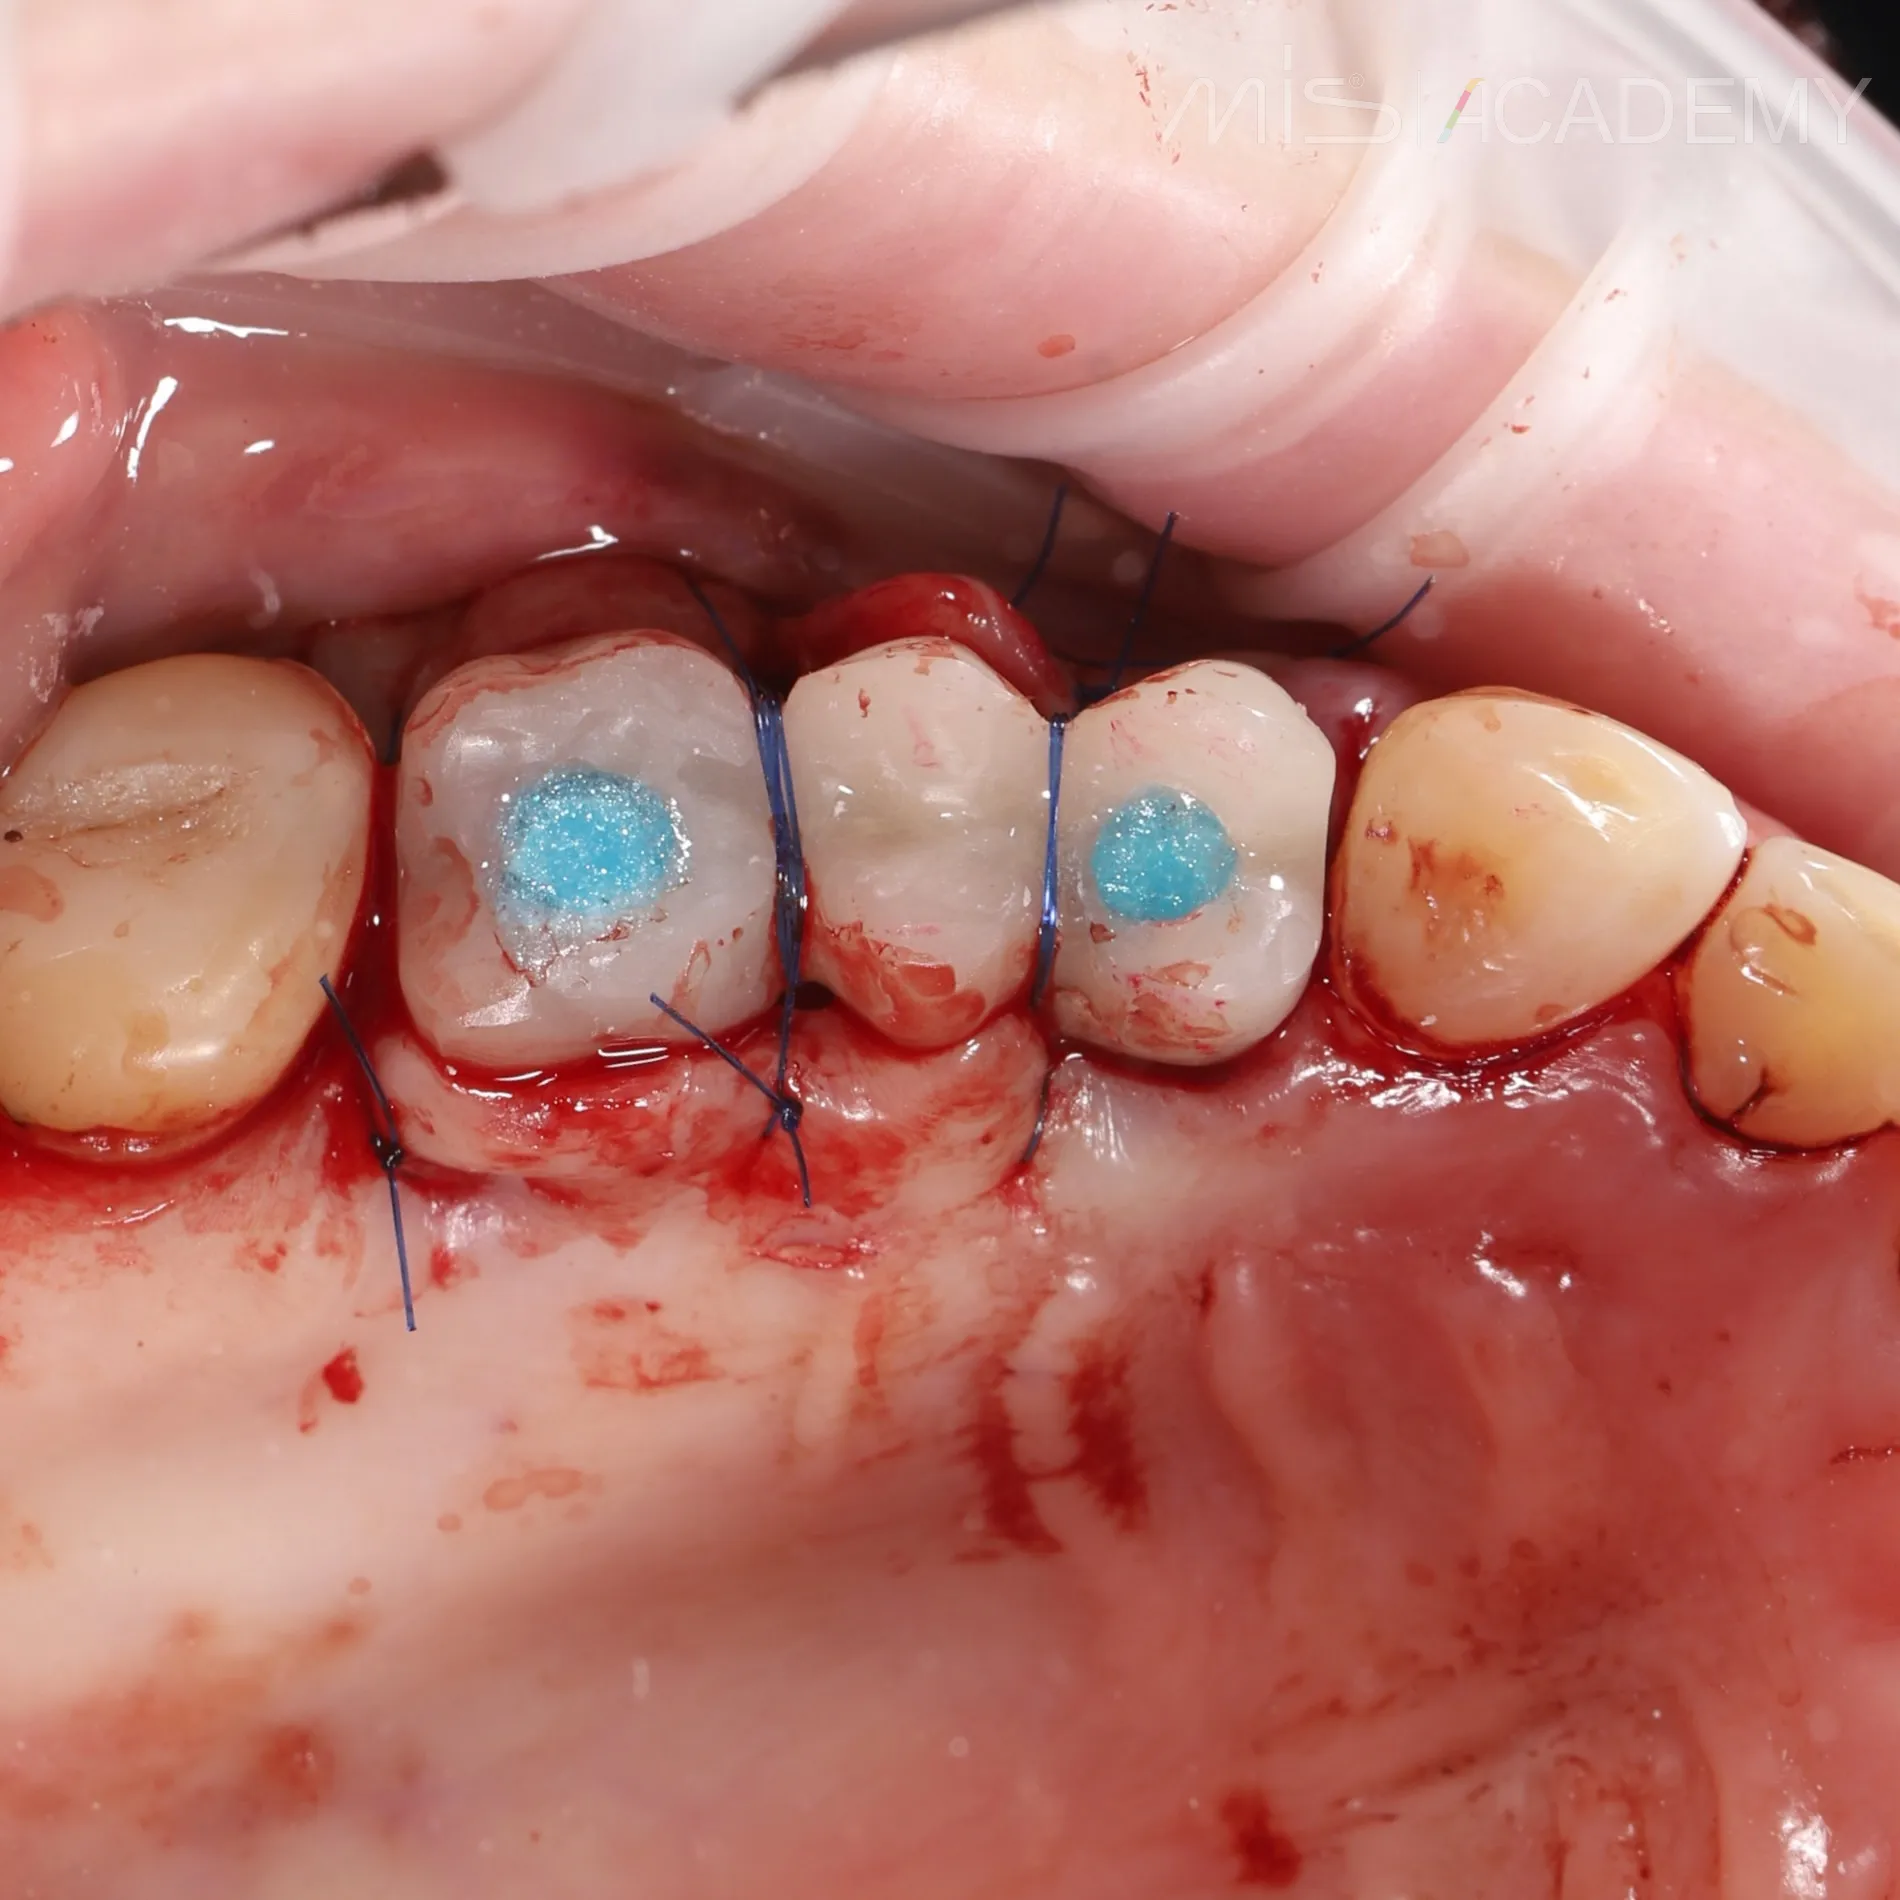

— Одномоментная установка имплантата в области 2.4.

— Установка имплантата в области 2.6 с закрытым синус-лифтингом.

— Установка произведена с помощью хирургического шаблона.

— Импланты MIS C1 3.75×13 и 4.2х8.

— Установлены multi unit в области 2.6.

— Connect- абатмент в области 2.4.

— Фиксация балки lego bridge + внутриротовая сварка.

— Временные коронки.

— Накладывание двойных обвивных швов.